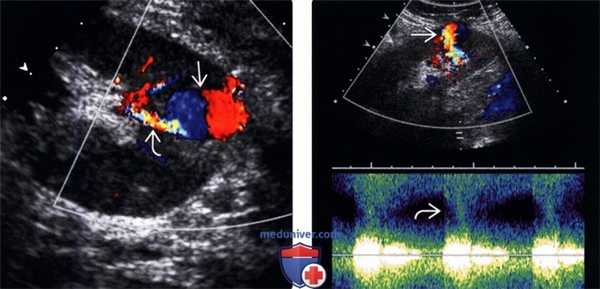

(Левый) На продольном УЗ срезе с цветовой допплерографией визуализируется псевдоаневризма в нижнем полюсе трансплантата почки. Представлен внутренний вихревой поток по типу «инь-ян». Цветовой дефект наложения питающей артерии.

(Правый) На продольном УЗ срезе со спектральной допплерографией псевдоаневризмы визуализируется хаотичный турбулентный кровоток в основании псевдоаневризмы.